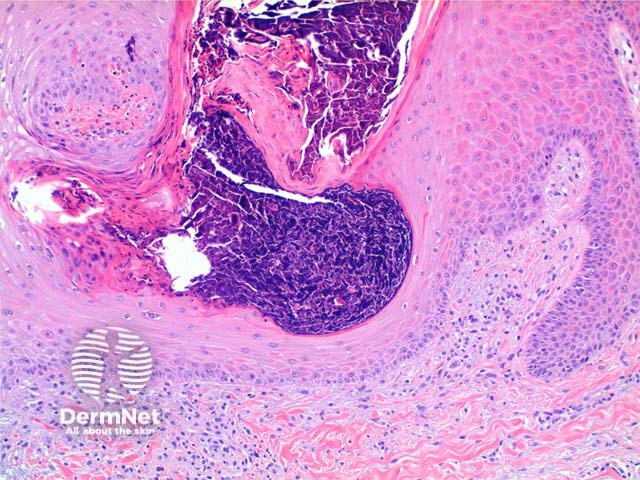

The low power view of perforating collagenosis shows an invaginating epidermal process (Figure 1). There is hyperkeratosis overlying a cup shaped depression or invagination in the epidermis. There is prominent epidermal hyperplasia, which encompasses a central basophilic plug of keratin, collagen and inflammatory debris (Figure 2). On careful sectioning, this is continuous with altered collagen in the underlying dermis, which is being expelled by the process of transepidermal elimination. Within the epidermal plug bright eosinophilic altered collagen fibres can be seen (Figures 3 and 4).

Figure 2